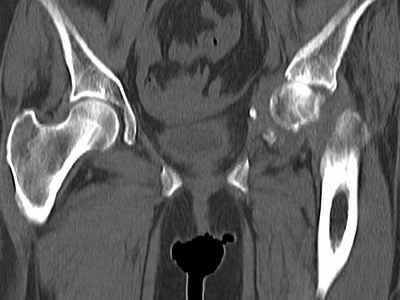

Уважаемые коллеги, возник вопрос по лечению нашей пациентки 60 лет. Около года назад множественная травма: в том числе Т-образный перелом вертлужной впадины. На сегодняшний день сращение отломков имеется на ограниченных участках, имеется дефект задней колонны вертлужной впадины. Движения неплохие, ходит с костылями, приступая на ногу. По мнению эдопротезистов при установке антипротрузионного кольца или октопуса не хватит костного материала и необходимо перед протезированием выполнить реконструкцию впадины, иначе чашка протеза неминуемо выпадет.Просьбы поделиться положительным и отрицательным опытом протезирования в подобных случаях.Возможно ли обойтись без реконструкции?Или лучше с ней?С уважением РАВ.